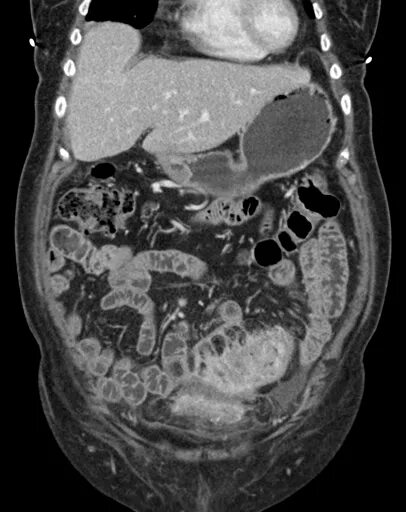

Метастазы при раке сигмовидной кишки